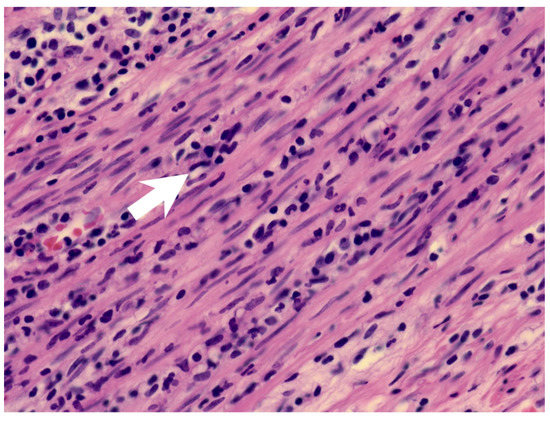

| Our patient | Yes | Hyperemic and engorged appendix with fibrin coating | Yes | Complete KD |